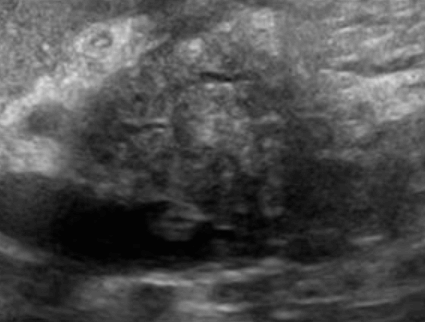

US finding

- 전반적으로 에코가 거칠게 보이는 간경변의 초음파소견과 비슷하여 주의가 필요함.

- 크기가 비슷한 고에코 또는 저에코 병변들이 보인다.

- 다중반사에 의한 comet-tail artifact를 보인다.